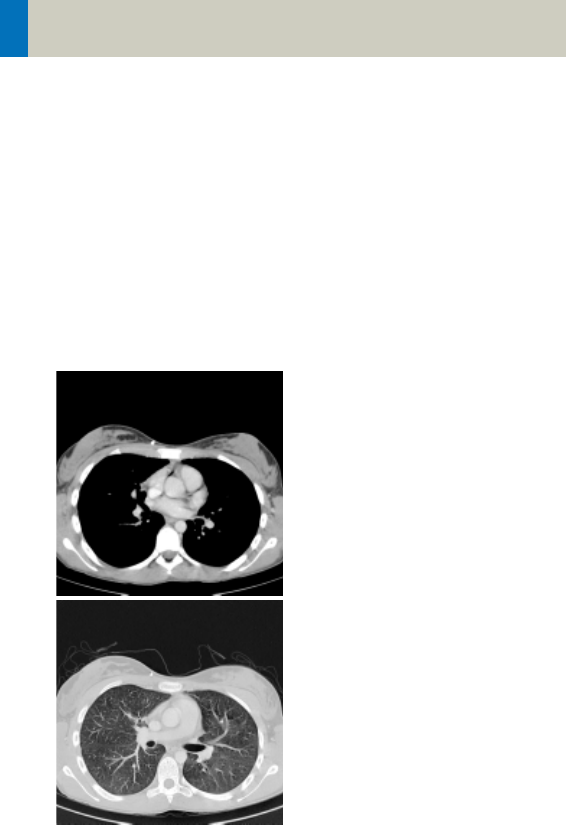

Thorax

ThoraxRoutine/

ThoraxRoutine08s

Indications:

Routine spiral studies for the region of thorax, e.g.,

examination of tumors, metastases, lymphoma, lymph

nodes, vascular anomalies etc.

A range of 30 cm will be covered in 23/18 sec.